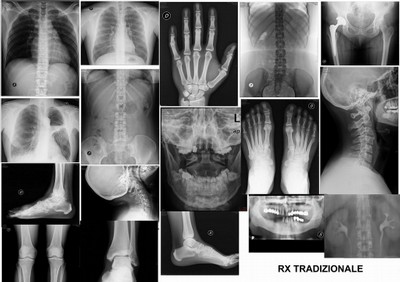

L'allarme dei radiologi: "Un esame radiografico su tre è inutile"

"Non solo spreco, ma anche rischi per il paziente"

Vai alla fonte

La stima è della Società Italiana di Radiologia Medica ed è stata diffusa in occasione del convegno per il suo centenario, dal tema “L’innovazione in radiologia per la medicina di domani”. Faletti: “Rendere gli esami più performanti in termini diagnostici e ridurre l’esecuzione di quelli inutili".

In Italia una prestazione radiografica su 3 è inutile. Se si considera che il costo per ogni esame, a seconda delle metodiche impiegate (si va dai 20 € di un semplice esame radiologico ai 150-200 € di una risonanza magnetica), incide comunque sulla gestione sanitaria, specie per TC e RM, e che ogni anno si fanno circa 1 milione di prestazioni radiologiche, si può immaginare quanto ci perda lo Stato.

La stima è della Società Italiana di Radiologia Medica, una delle più antiche associazioni di categoria del settore medico e, nello specifico, dei professionisti di radiologia (circa 10.000 gli associati), che, in occasione della celebrazione del convegno per il suo centenario, dal tema “L’innovazione in radiologia per la medicina di domani”, cerca di dare delle risposte costruttive a questo problema. Rendere gli esami più performanti in termini diagnostici e ridurre l’esecuzione di quelli inutili sono le due scommesse per il futuro lanciate da SIRM e ufficializza la propria adesione al progetto “Fare di più non significa fare meglio”.